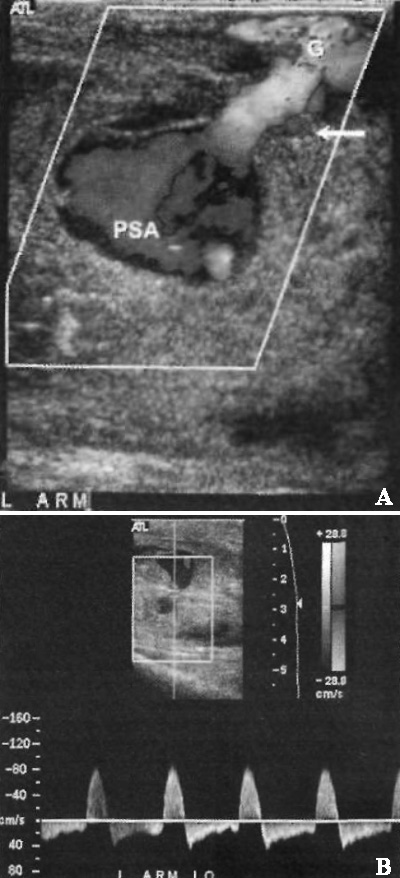

Ложная аневризма визуализируется как эхогенное образование, локализованное вне просвета шунта. Цветовая допплерография демонстрирует двунаправленный поток; спектральная допплерография в области шейки аневризмы демонстрирует альтернирующий кровоток над и под изолинийе. При диагностике ложной аневризмы необходимо обнаружить ее шейку в месте отхождения от шунта (фото 4).

Фото 4. Ложная аневризма. А – цветовая допплерограмма шунта (G): стрелкой обозначена шейка, которая соединяет шунт с ложной аневризмой (PSA). В – спектральная допплерограмма шейки ложной аневризмы: наблюдается поток «туда-сюда», обусловленный наполнением и оттоком крови из аневризмы (сигнал регистрируют под нулевой линией)

Также цветовая допплерография помогает дифференцировать псевдоаневризму со скоплением жидкости: ложная аневризма визуализируется как типичный мозаичный крутящийся поток внутри плотного образования, тогда как скопление жидкости представляет собой гипоэхогенное образование без каких-либо допплеровских сигналов.